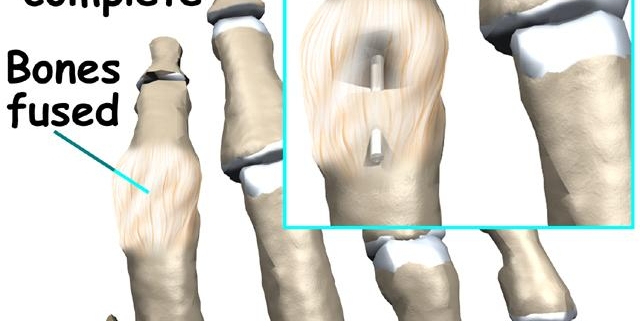

Finger fusion surgery, also known as arthrodesis, is a surgical procedure designed to fuse bones in a joint to minimize joint pain and enhance stability. It’s a treatment option often considered for patients with severe arthritis pain in their fingers or those who’ve experienced a serious finger injury. While it’s not as common as other types of joint surgeries like hip or knee replacements, finger fusion surgery still plays a vital role in improving the quality of people’s lives.

If these approaches fail to deliver relief, surgery such as joint fusion may be recommended. This procedure involves removing the surface of the joint and using a combination of screws, wires, or plates to join the bones together.